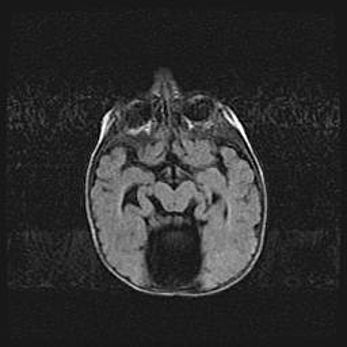

Наружная гидроцефалия с возможной атрофией височных областей.

Возраст: 28 дней

Вес: 3670 г

Пол: мужской

Окружность головы: 38 см

Срок гестации: 40 недель

Гидроцефалия головного мозга у новорожденных – это заболевание, которое характеризуется скоплением избыточного количества спинномозговой жидкости в желудочковой системе головного мозга в результате затруднения её перемещения от места выработки к месту поглощения в кровеносную систему или вследствие нарушения абсорбции. При открытой наружной форме гидроцефалии у новорожденных расширяются и переполняются субарахноидные пространства.

При нормотензивных  формах,  которые,  как  правило,  являются  следствием  перенесенных ишемических  повреждений  паренхимы  мозга,  возможно  сочетание микроцефалии  с нормотензивной гидроцефалией. В основе данных изменений лежит атрофия больших полушарий с преимущественной  локализацией  в  лобно-височных  областях.